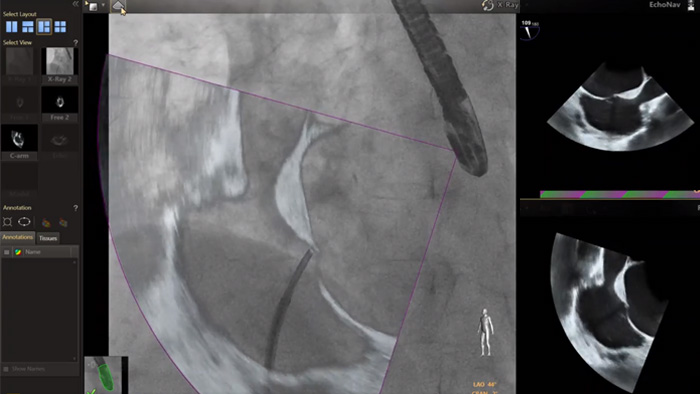

Au cœur de notre suite, la solution unique EchoNavigator est un bon exemple de l’engagement de Philips en faveur de la multimodalité et de l’intégration des processus de travail, en offrant les avantages des deux systèmes de la part du leader du secteur des solutions cardiaques interventionnelles par rayons X et par ultrasons.

Guidage de ponction transseptale à l’aide d’EchoNavigator

Optimisation de la vue de la valve mitrale avec les modèles cardiaques EchoNavigator

Optimisation de la vue de la valvule tricuspide avec les modèles cardiaques EchoNavigator

Visualisation des valves mitrale et aortique avec les modèles cardiaques EchoNavigator